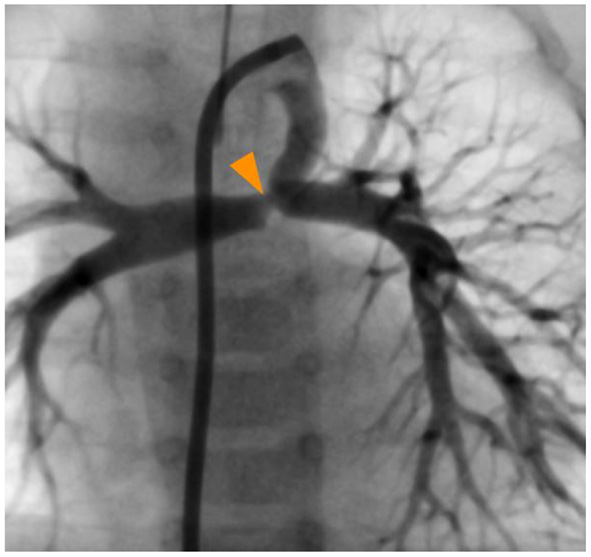

Figure 1

Ductal angiography showing the restricted pulmonary ductal (orange arrowhead) end and the absence of connection between the branch pulmonary arteries and the pulmonary artery trunk.